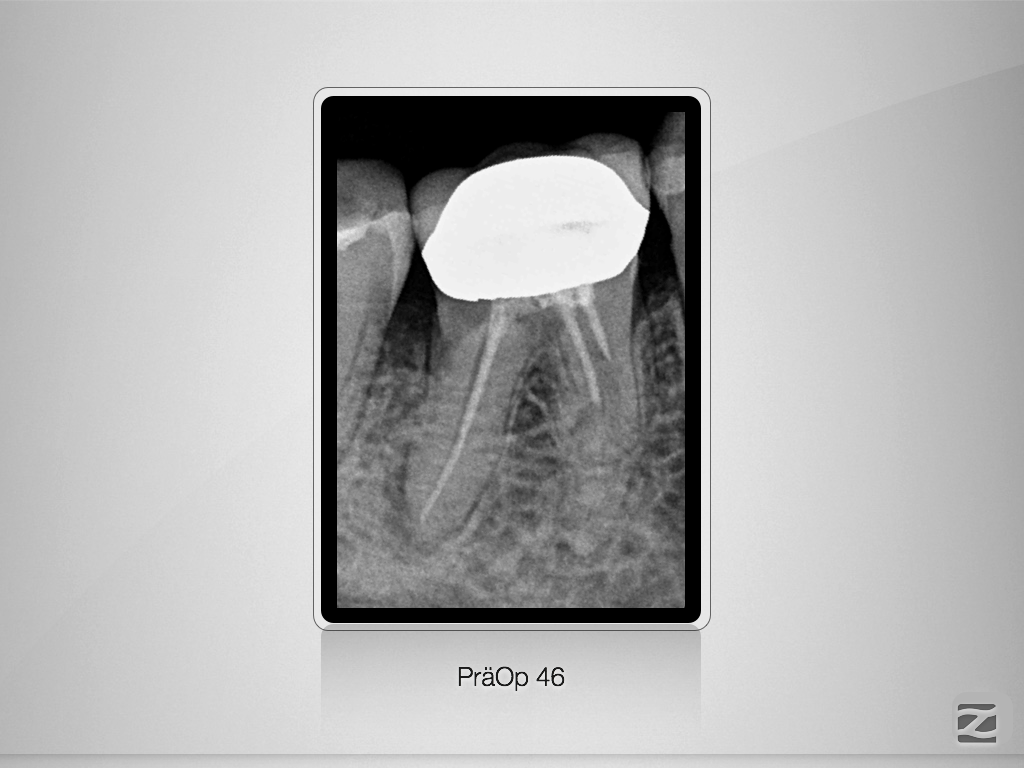

46D.001

2D vs. 3D (XXVIV)